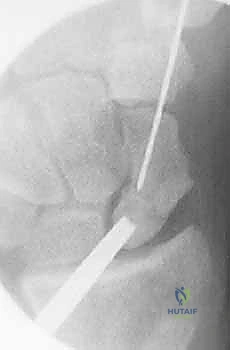

هذه هي التقنية المتقدمة التي يبرع فيها الأستاذ الدكتور محمد هطيف في صنعاء. بدلاً من فتح الرسغ، يتم إجراء العملية بأكملها من خلال شقوق دقيقة لا تتجاوز 2-3 مليمترات، تحت إرشاد جهاز الأشعة المرئية (Fluoroscopy) وبمساعدة المنظار المفصلي الدقيق.

العملية الجراحية بتقنية التدخل المحدود ليست مجرد "إدخال مسمار"، بل هي عمل فني وهندسي دقيق يتطلب مهارة جراحية فائقة، تخطيطاً مسبقاً، وتنسيقاً مثالياً بين يدي الجراح والصور الإشعاعية. يتبع الأستاذ الدكتور محمد هطيف بروتوكولاً صارماً لضمان أعلى معدلات النجاح.